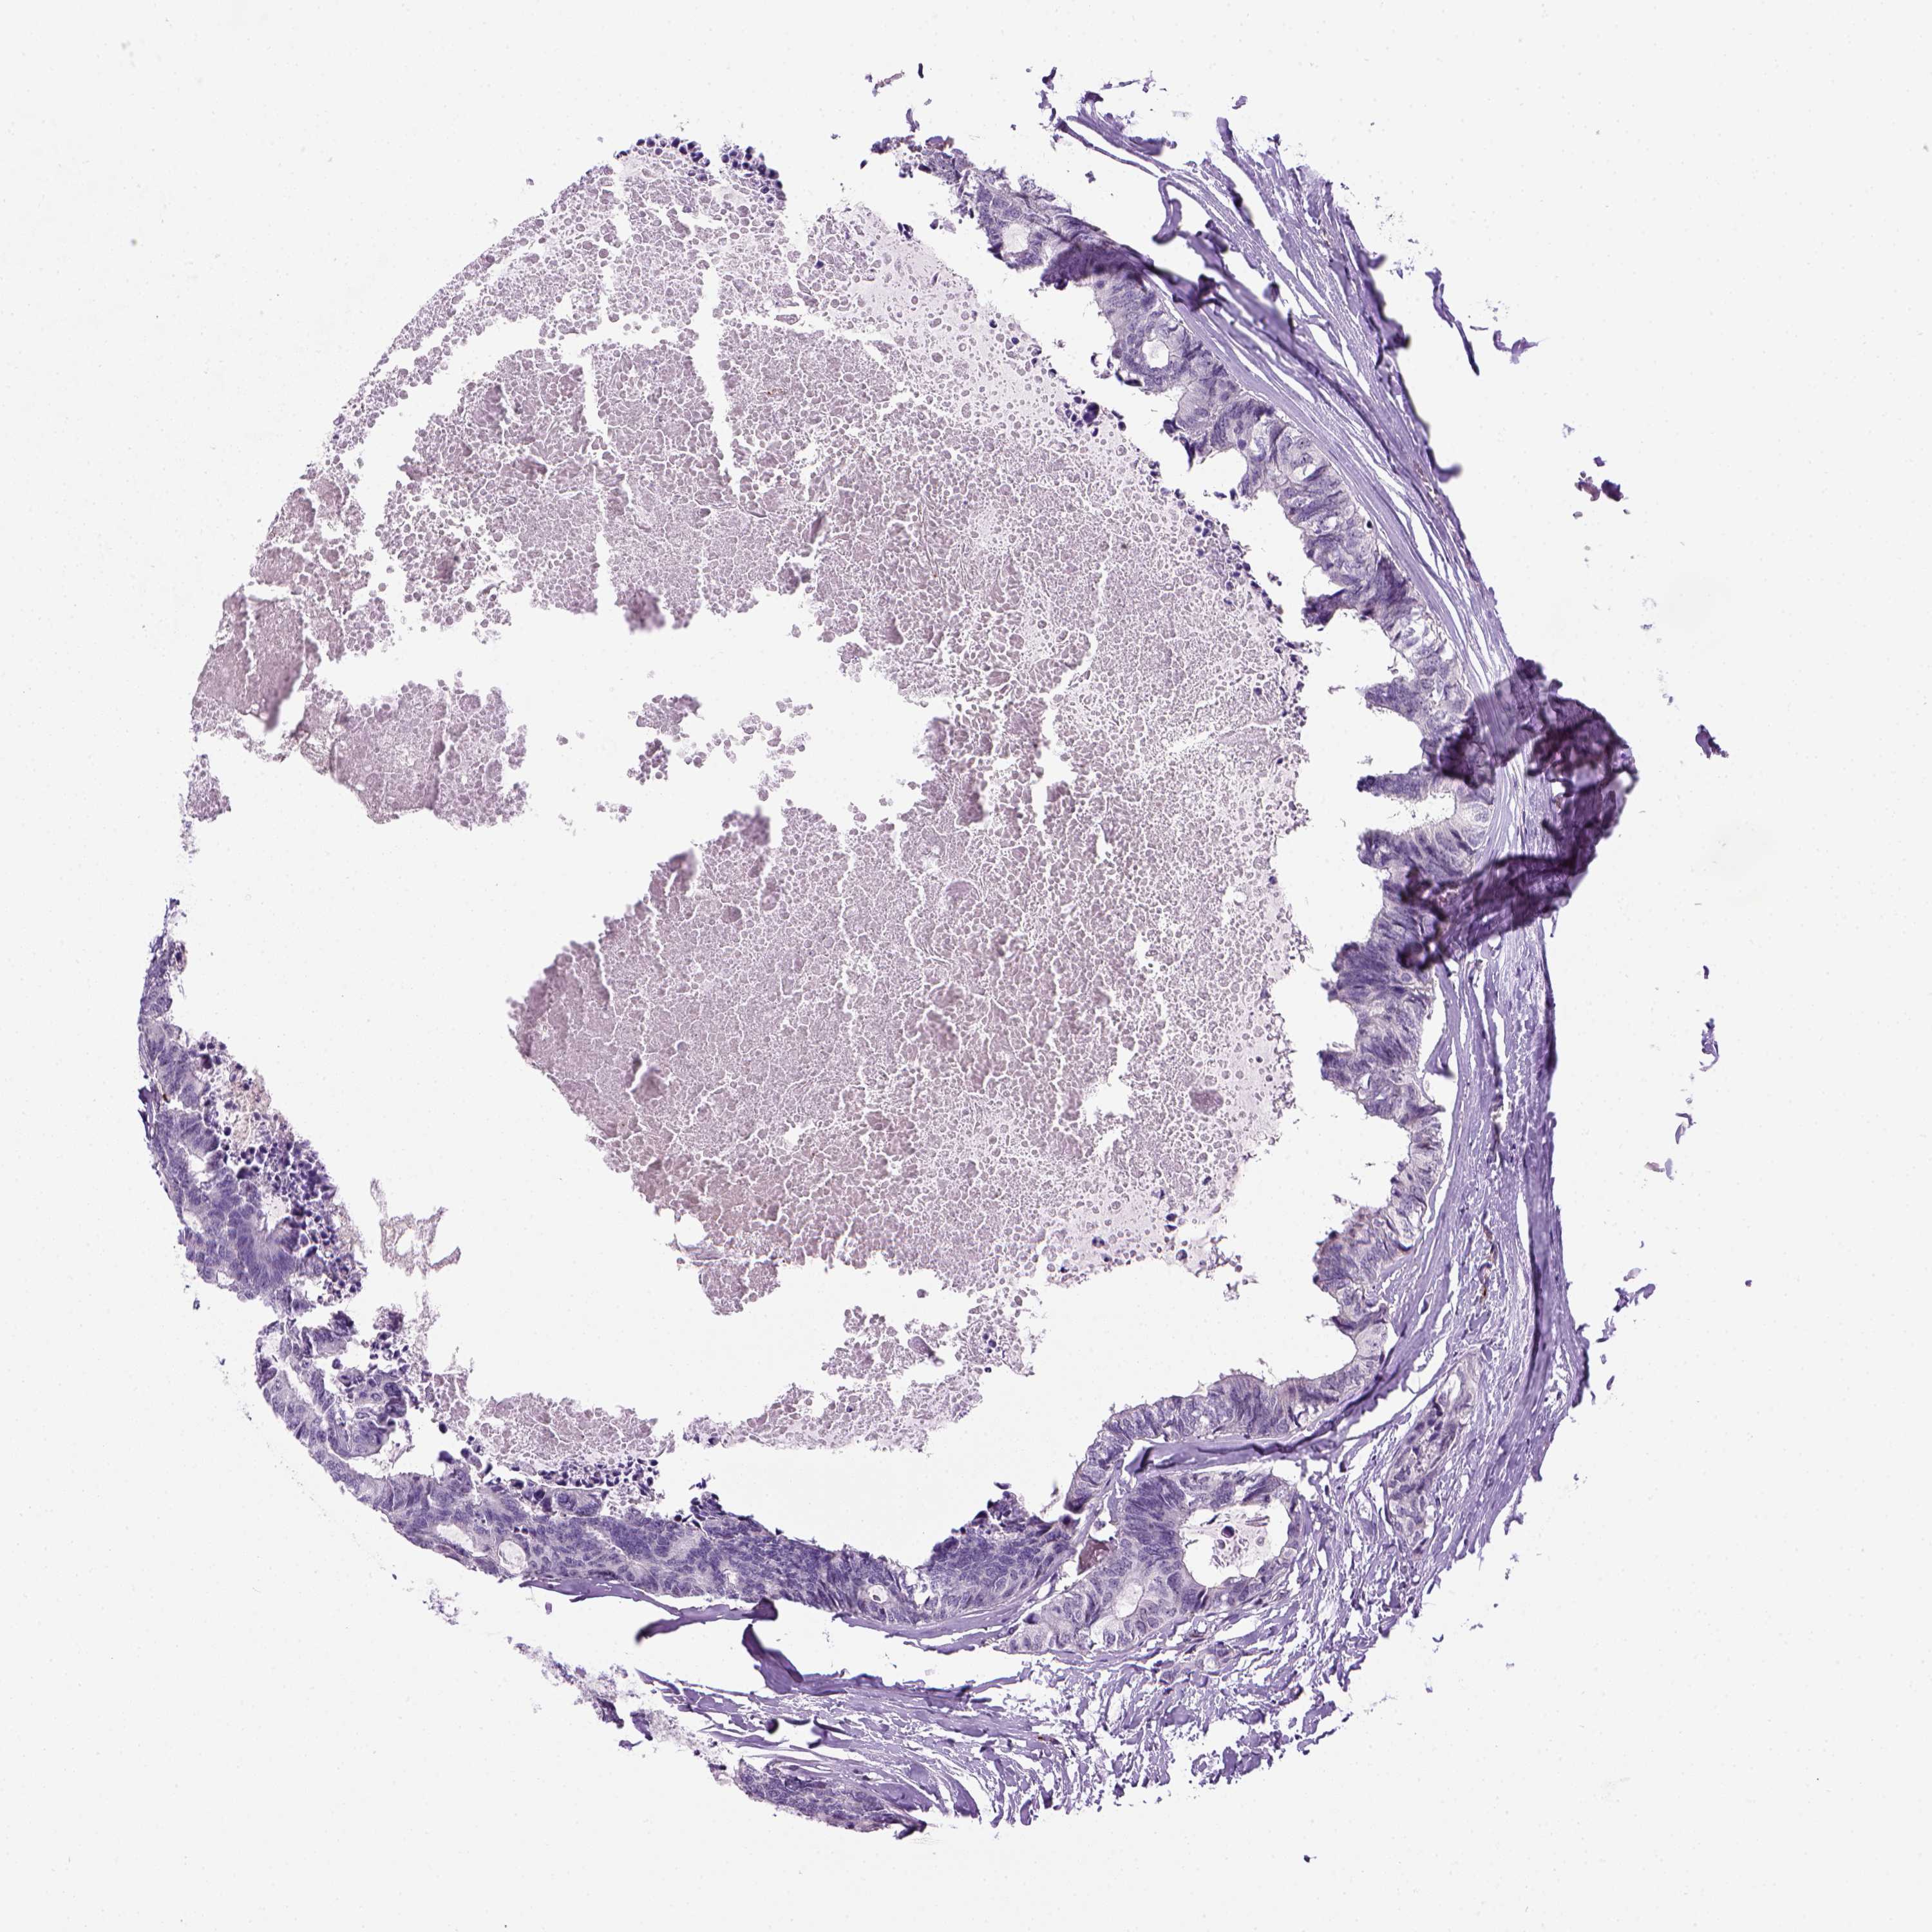

CANCER COLORECTAL CANCER Show tissue menu

COAD TCGA COAD VALIDATION READ TCGA READ VALIDATION PROTEIN COAD CPTAC PROTEIN EXPRESSION

ANTIBODIES

AND

VALIDATION